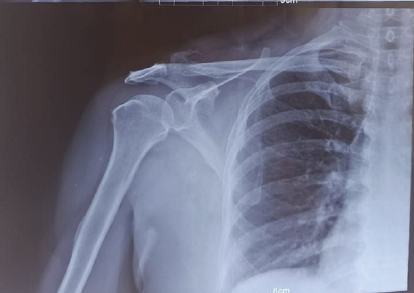

Bipolar Clavicle Fracture in Elderly: A Rare Case Report

A S Arun Kumar , B Bidhu , G Ranjit Kumar , Vishnu Harikrishnan

………………………………p.58-62